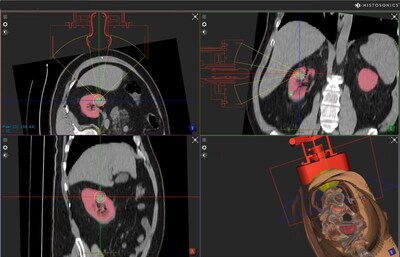

Company to Utilize its New Edison™ System with Advanced Imaging Features for Use in Kidney Tumors

“We are very pleased with the FDA’s approval of our #HOPE4KIDNEY Trial and appreciative of the agency’s prompt review process. This approval represents a substantial milestone for our company as we continue to expand histotripsy and its potential benefits into diseases that impact the lives of so many people,” commented Mike Blue, President and CEO of HistoSonics. Blue added, “We are excited to expand on our experiences in successfully targeting and treating in the liver using our enhanced Edison platform that combines advanced imaging and targeting capabilities with real time treatment monitoring. The kidney is a logical next application as treating in the kidney has very similar procedural and anatomical considerations as the liver, and Edison was specifically designed to treat anywhere in the abdomen, as a starting point. In addition, the prevalence of kidney disease remains high with many patients kept in active surveillance or watchful waiting.”

HistoSonics’ image guided sonic beam therapy system uses advanced imaging and proprietary sensing technology to deliver non-invasive, personalized treatments with precision and control. The science of histotripsy uses focused sound energy to produce controlled acoustic cavitation that mechanically destroys and liquifies targeted liver tissue at sub-cellular levels. The company believes that the novel mechanism of action of their proprietary technology provides significant advantages to patients, including the ability of the treatment site to recover and resorb quickly. Uniquely, the HistoSonics’ platform also provides physicians the ability to monitor the destruction of tissue under continuous real-time visualization and control, unlike any modality that exists today.

Photo – https://mma.prnewswire.com/media/2000594/Kidney_Simulation_image_for_PR_v3.jpg

Company to Utilize its New Edison™ System with Advanced Imaging Features for Use in Kidney Tumors

“We are very pleased with the FDA’s approval of our #HOPE4KIDNEY Trial and appreciative of the agency’s prompt review process. This approval represents a substantial milestone for our company as we continue to expand histotripsy and its potential benefits into diseases that impact the lives of so many people,” commented Mike Blue, President and CEO of HistoSonics. Blue added, “We are excited to expand on our experiences in successfully targeting and treating in the liver using our enhanced Edison platform that combines advanced imaging and targeting capabilities with real time treatment monitoring. The kidney is a logical next application as treating in the kidney has very similar procedural and anatomical considerations as the liver, and Edison was specifically designed to treat anywhere in the abdomen, as a starting point. In addition, the prevalence of kidney disease remains high with many patients kept in active surveillance or watchful waiting.”

HistoSonics’ image guided sonic beam therapy system uses advanced imaging and proprietary sensing technology to deliver non-invasive, personalized treatments with precision and control. The science of histotripsy uses focused sound energy to produce controlled acoustic cavitation that mechanically destroys and liquifies targeted liver tissue at sub-cellular levels. The company believes that the novel mechanism of action of their proprietary technology provides significant advantages to patients, including the ability of the treatment site to recover and resorb quickly. Uniquely, the HistoSonics’ platform also provides physicians the ability to monitor the destruction of tissue under continuous real-time visualization and control, unlike any modality that exists today.

Photo – https://mma.prnewswire.com/media/2000594/Kidney_Simulation_image_for_PR_v3.jpg